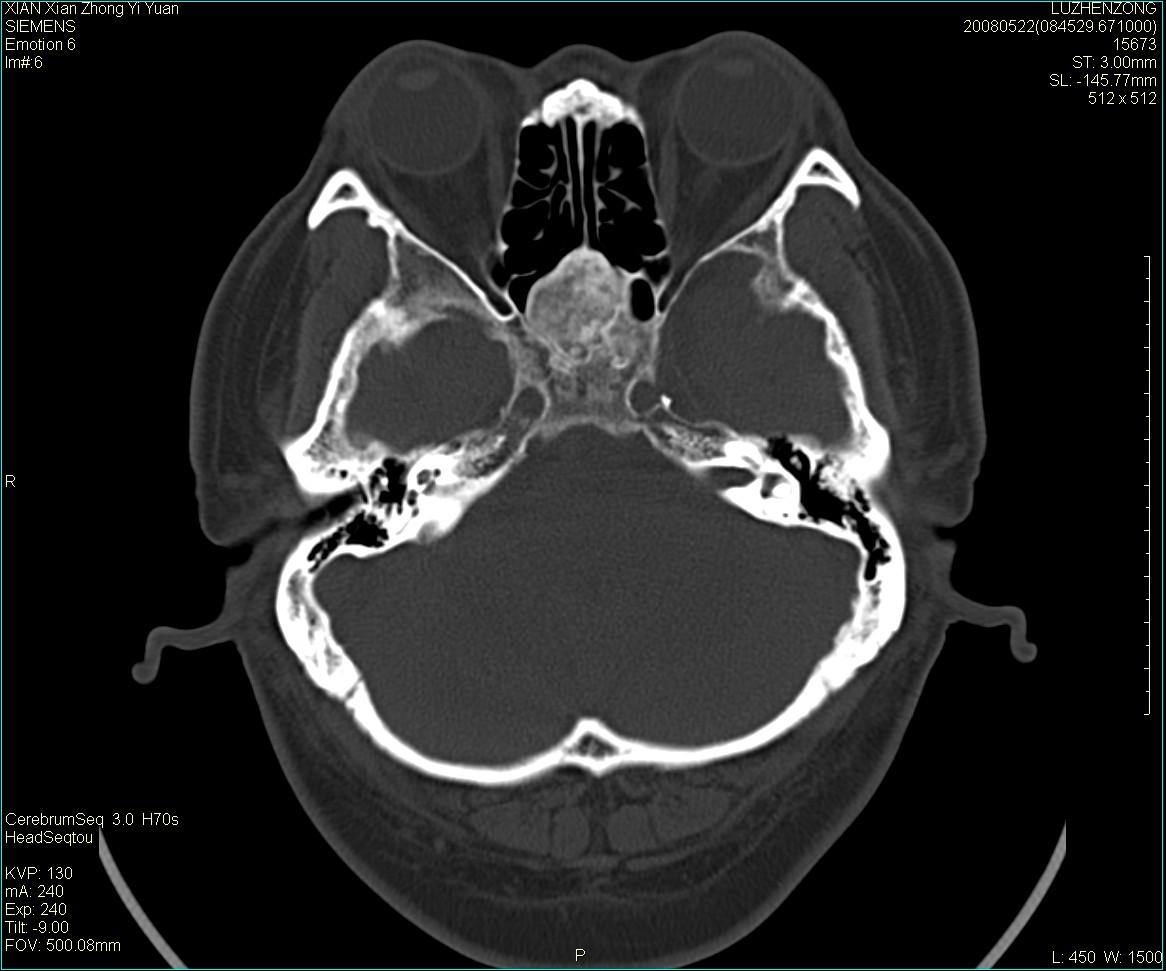

以下是引用gaoshengjiang在2008-5-28 19:06:00的发言:[br]考虑来源于蝶骨前床突区骨软骨瘤。

以下是引用卜一在2008-5-28 20:46:00的发言:[br]中颅窝“骨纤维异常增殖症”。不除外考虑来源于蝶骨前床突区“骨软骨瘤”。[br]

以下是引用liangshusheng在2008-5-28 20:13:00的发言:[br]单骨病变,考虑骨化性纤维瘤。